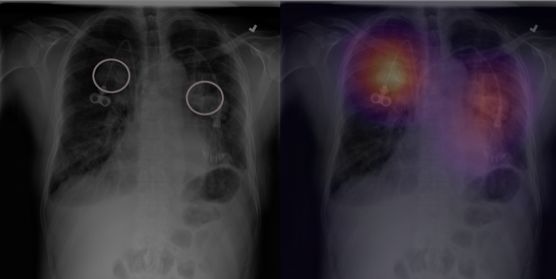

Deep learning for chest radiograph diagnosis: A retrospective comparison of the CheXNeXt algorithm to practicing radiologists

胸部X光是检测很多疾病的重要手段,例如肺结核或肺癌。然而,检查过程通常需要有经验的专业医生进行诊断,很多地区缺少专门的放射科医生,往往导致病情延误。现在,研究者提出了一种基于深度学习的方法,能在医学图像处理中达到人类专家的水平。本文就介绍了这样一种名为CheXNeXt的卷积神经网络,可以检测出14种疾病。